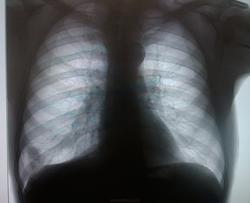

Периферический c-r нижней доли правого легкого (S8), отрицательная динамика в сравнении с исследованием от 2011 г. Показано дообследование : КТ (уточнение характера образования; исключение метастатических очагов; состояние л/узлов); трансторакальная пункция (морфологическая верификация).

Для начала - пневмония в S8 справа. Р-контроль после лечения поможет с окончательным вердиктом.

Думается о периферическом в S10

кстати, в 2011 году там уже нечисто похоже

на прямом связи образования с позвоночником не видно.. может мезотелиома какая

участок фиброза с кальцинатами, онконастороженность. Но может быть туберкулема?

больше данных за периферическое образование в S8, лучше направить на консультацию к онкологам.

В сравнении с архивом-медленная отрицательная динамика,есть плевральное дело,больше за онкологию в нижней доле.

Периферический с дорожкой.

Думается периферический в С 8, дообследование обязательно КТ или томография

Нет. Только кашель редкий. Спасибо большое Всем за мнения. Тоже больше за периферический c-r S8.

Добавлю и своё видение. Периферический в S9, с учётом косой боковой проекции, туда отправлю его.

Мне как-то видится не одна тень в 8(9)-ке, а ребро еще. Может, кажется. И корень тоже задействован. "Зло"